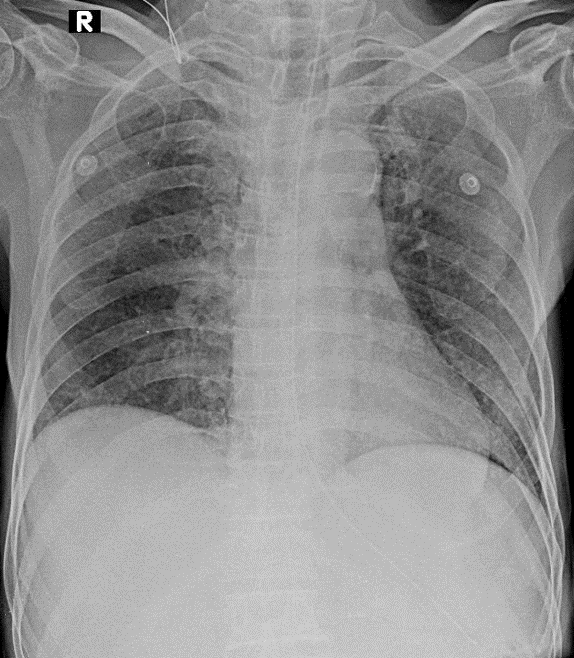

Hãy phân tích tình huống Nam 89 tuổi

1-Thâm nhiễm mô kẻ rải rác hai phổi (P)>(T)=> VIÊM PHỔI